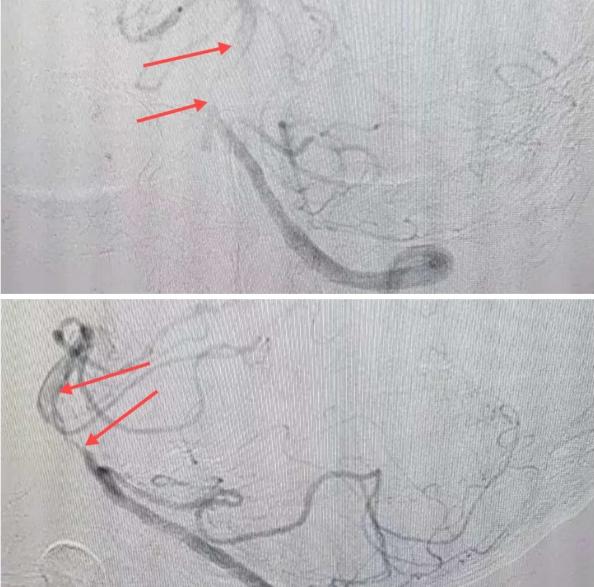

在經(jīng)造影后,主刀醫(yī)生腦一科副主任楊慶堂發(fā)現(xiàn)患者基底動脈下段重度狹窄且狹窄段以遠有大負荷血栓,其狹窄處考慮為動脈夾層,手術(shù)難度及風(fēng)險較大。楊慶堂副主任在彭壯副主任醫(yī)師的協(xié)助下運用spaceman(太空人)技術(shù),中間導(dǎo)管抵近血栓抽吸配合支架拉栓,成功開通血管。再次造影可見基底動脈管腔明顯增寬,遠端血管顯影良好,且等待20分鐘后造影仍顯示血流通暢。楊慶堂副主任考慮到本次手術(shù)時間不宜過長,現(xiàn)患者基底動脈及分支前向血流維持良好,給予其抗栓藥物應(yīng)用后結(jié)束手術(shù),并建議患者3個月后復(fù)查造影,明確其基底動脈夾層情況。

造影可見血管夾層和大量血栓形成

取栓后血管管腔增寬,前向血流良好